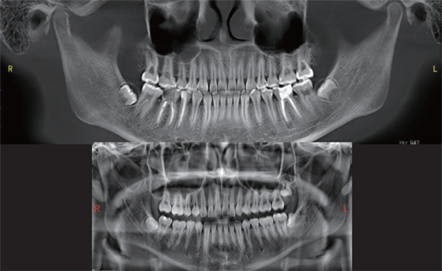

Additionally, the system provides three flexible scan modes to match clinical needs. Multiple focus layers in panoramic imaging fit each patient’s dental arch perfectly.

T-MAR Metal Artifact Reduction

Multiple focus layers in panoramic imaging, fitting the patient’s dental arch

Multiple focus layers in panoramic imaging, fitting the patient’s dental arch -

With the new T-MAR module, the system automatically removes metal artifacts and corrects image distortions intelligently.

Hence, the final images remain clear, accurate, and clinically reliable.

Furthermore, AI+PAN Dental CBCT Imaging enhances precision.

- The system rebuilds panoramic views directly from CBCT data using AI.

- Panoramic auto-focus and multi-layer technology select the best curve automatically.

- Therefore, the final image is cleaner and easier to read.